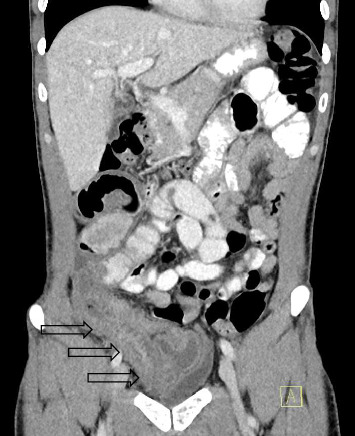

The objectives were to highlight that: (1) mesh erosion related partial small bowel obstruction after laparoscopic totally extraperitoneal (TEP) inguinal hernia repair (IHR) as an uncommon complication can clinically and radiologically mimic ileocolic Crohn's disease in young adults; and (2) implore clinicians to consider a broad set of differential diagnosis and prompt involvement of other subspecialties, especially if preliminary investigations and treatment yield minimal results. The authors report a 34-year-old male who presented with computed tomography (CT) findings of ileitis, which was initially investigated for Crohns' disease. Due to persisting abdominal pain and negative initial investigations, he underwent a laparotomy demonstrating secondary mesh migration with erosion into distal ileum requiring bowel resection, 2.5 years after an uneventful laparoscopic right TEP IHR. The patient made an uneventful postoperative recovery and at 6 weeks follow-up, he had resolution of abdominal pains, and normal bowel function.